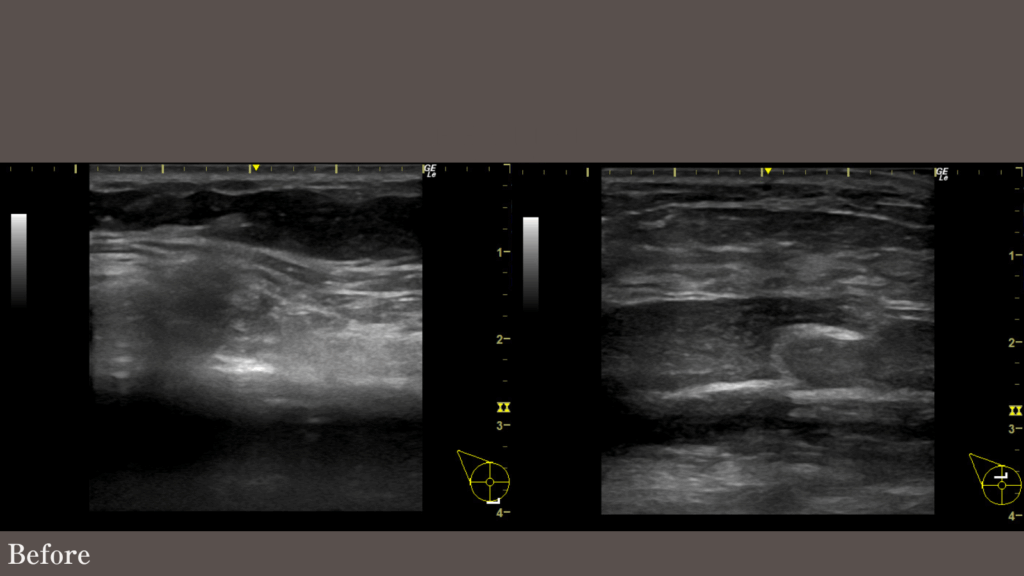

39歳女性 右胸のアクアフィリング除去を行っています。左胸は感染のため、入院して除去されたとのことです。

バスト下縁に落ち込み、形が崩れています。